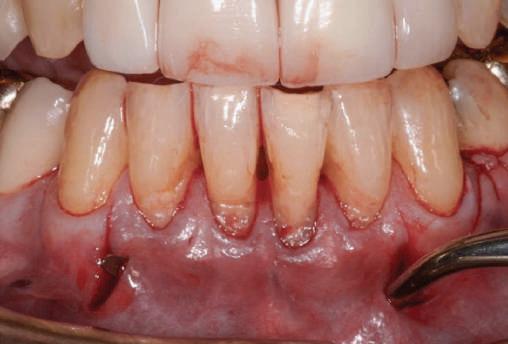

Cazul (3)

Refrezarea bonturilor individualizate

Pacientul prezenta dentiţie maxilară şi mandibulară eşuată datorită cariei secundare provocată de xerostomia post-iradiere. Pacientul suferise o disecţie cervicală radicală pentru înlăturarea carcinomului cu celule scuamoase la nivelul gâtului cu 9 ani înainte, urmată de radioterapie dar fără limită de ecranare. S-a utilizat o abordare stadializată pentru a evita protezele mobilizabile pe ţesuturile moi, extrem de uscate. Pacientul a optat pentru tratarea prioritară la nivel mandibular.

Fig. 9 prezintă bonturile de vindecare adiacente dinţilor naturali menţinuţi temporar, iar fig. 10 bonturile individualizate din prima etapă, inserate cu un contur gingival relativ bun şi fără recesie. Recesia era clar vizibilă în jurul tuturor bonturilor din prima etapă, după extracţiile adiacente şi plasarea implanturilor din a doua etapă (fig. 11). Atitudine: S-a decis îndepărtarea acestor bonturi şi amprenta corpului implantar al tuturor implanturilor astfel încât bonturile noi şi cele din prima etapă să fie frezate împreună pentru paralelism şi poziţionarea adecvată a marginii gingivale. Întrucât aceasta necesita îndepărtarea bonturilor din prima etapă care menţineau proteza provizorie, înainte de îndepărtarea tuturor bonturilor individualizate s-au plasat bonturi provizorii, cu scopul de a asigura poziţionarea adecvată şi dimensiunea verticală a restaurării provizorii. Aceste bonturi provizorii au menţinut apoi restaurarea temporară,

Cazul (3): Refrezarea bonturilor individualizate

Figurile

9. Bonturile de vindecare.

10. Bonturile individualizate în prima etapă.

11. Recesia evidentă în jurul bonturilor din prima etapă, după extracţiile adiacente şi inserarea implanturilor din faza a doua.

12. Bonturile refrezate şi noile bonturi individualizate.

în timp ce toate bonturile individualizate au fost fabricate şi/sau frezate în laborator. Fig. 12 prezintă plasarea bonturilor refrezate (la implanturile din prima etapă) şi bonturile individualizate noi (la cele din a doua etapă).